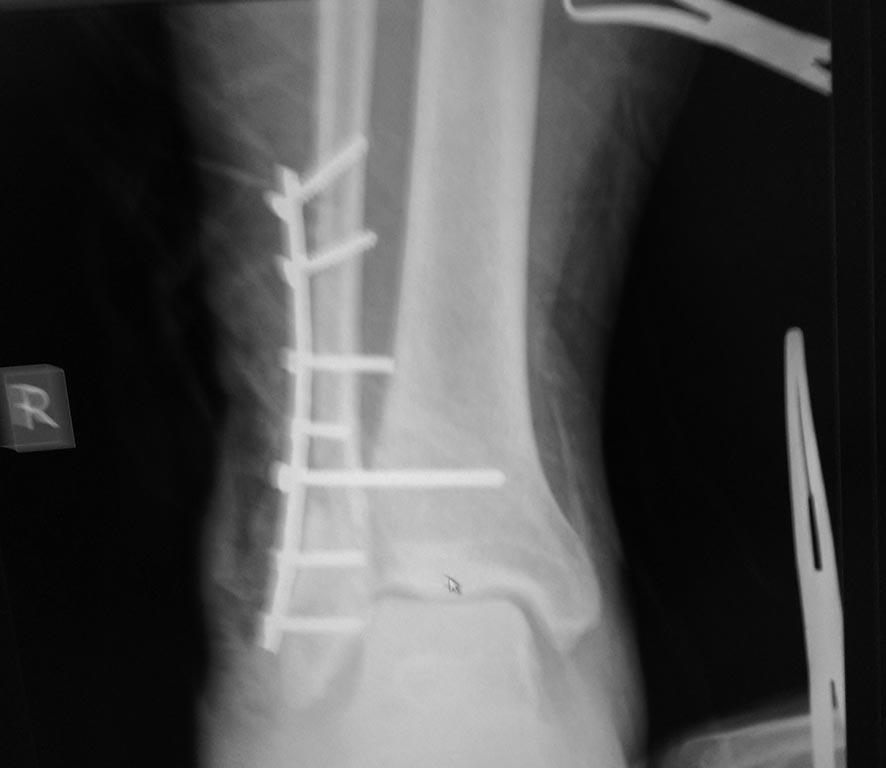

на следующий день

Вся беда в том, что снимки в операционной и после с разной ротацией голени. Репозиция нар. лодыжки не гут. Подвывих есть. Перфекционизм требует реостеосинтеза. Ваши действия будут зависеть от возраста, местного статуса, психики пациента и умения убедить без вреда для себя. Пластина не причём. Много лодыжек прооперировали реконструктивными пластинами. Главное репозиция.

Моё мнение, что ничего переделывать не нужно. Подвывиха стопы кнаружи у пациента нет. Есть подвывих кзади, так как пластинка лежит по передней поверхности малоберцовой кости, а синдесмозный винт выталкивает таранку кзади. Может через 2-2.5 мес после операции удалить винт, а может после нагрузки без удаления винта подвывих кзади устранится.

Здравствуйте. Есть рентгенограмма с переложенной гипсовой повязкой в нейтральной позиции, но только прямая проекция.

Я согласен с Андреем Петровичем. Чтобы выполнять реостеосинтез, нужно знать, что вы точно хотите улучшить и чем вы готовы пожертвовать (от осложнений никто не застрахован, а после реостеосинтеза шансы на это резко возрастают). На последней рентгенограмме подвывиха не вижу. На счет позиционного винта - мы бы удалили через 6-8 недель и интраоперационно выполнили бы рентгенконтроль.